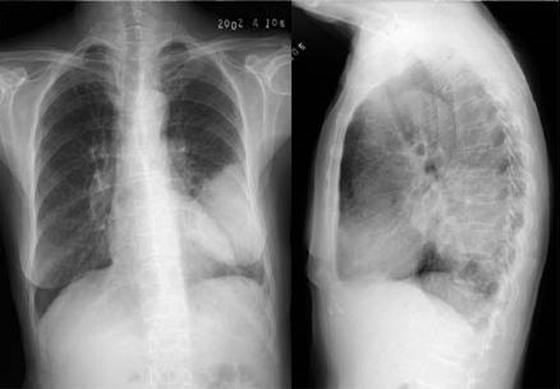

04卷-3.病史:男性,53歲,咳嗽、體重減輕4個月。診斷

A.左下肺炎

B.左下包裹性積液

C.左下肺癌

D.左下肺結(jié)核

題目解析:【該題針對“ X線-肺癌 ”知識點進行考核】